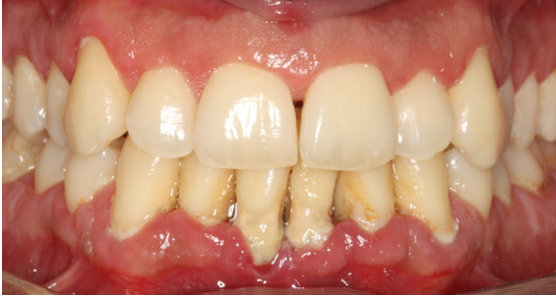

15. Θεραπεία χρόνιας περιοδοντίτιδας σε καπνιστή

Ο ασθενής ηλικίας 50 ετών παρουσίαζε περιοδοντική νόσο προχωρημένης βαρύτητας και ήταν βαρύς καπνιστής. Ανέφερε πόνο στα ούλα, αιμορραγία και έντονη κακοσμία. Παράλληλα με την περιοδοντική θεραπεία, δόθηκε έμφαση στη μείωση του καπνίσματος. Στην κλινική εικόνα κατά την επανεξέταση παρατηρείται απουσία φλεγμονής.

ΑΡΧΙΚΗ ΚΛΙΝΙΚΗ ΕΙΚΟΝΑ

ΤΕΛΙΚΗ ΚΑΤΑΣΤΑΣΗ